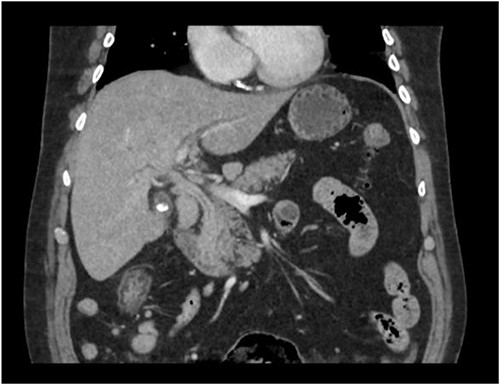

Repeat liver function test 1 month later showed dramatic improvement, with bilirubin level at 25 umol/L (normal 2–20), total IgG 13.23 g/L (normal 6.5–15.2), IgG4 1.45 g/L (normal 0.04–0.86), and CA19-9 44 (normal < 34). The steroids were gradually tapered and ceased. Repeat MRI 4 months later showed a normal biliary system with complete resolution of the common bile duct pathology (Fig. 4).